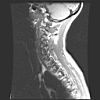

CWZ